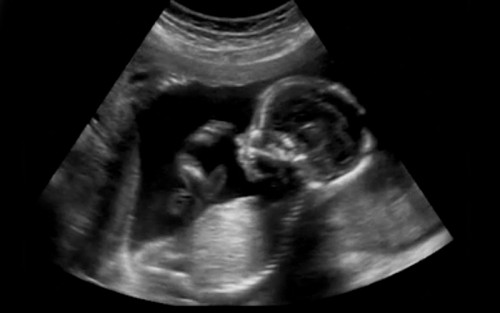

Histórias como a de Fátima da Conceição*, que hoje tem 46 anos, ressaltam que quando a grávida recebe o suporte para a gestação e a criação do filho, a escolha é sempre unânime: VIDA! Por isso, há 68 anos, a LBV ampara não apenas o bebê, mas a estrutura familiar, cuidar de uma criança é tarefa da mãe, do pai ou de todo aquele que desempenhar esses papeis. A Instituição entende, assim como a ciência pontua, que a vida existe desde o momento da fecundação e toda existência deve ser preservada a partir daí.